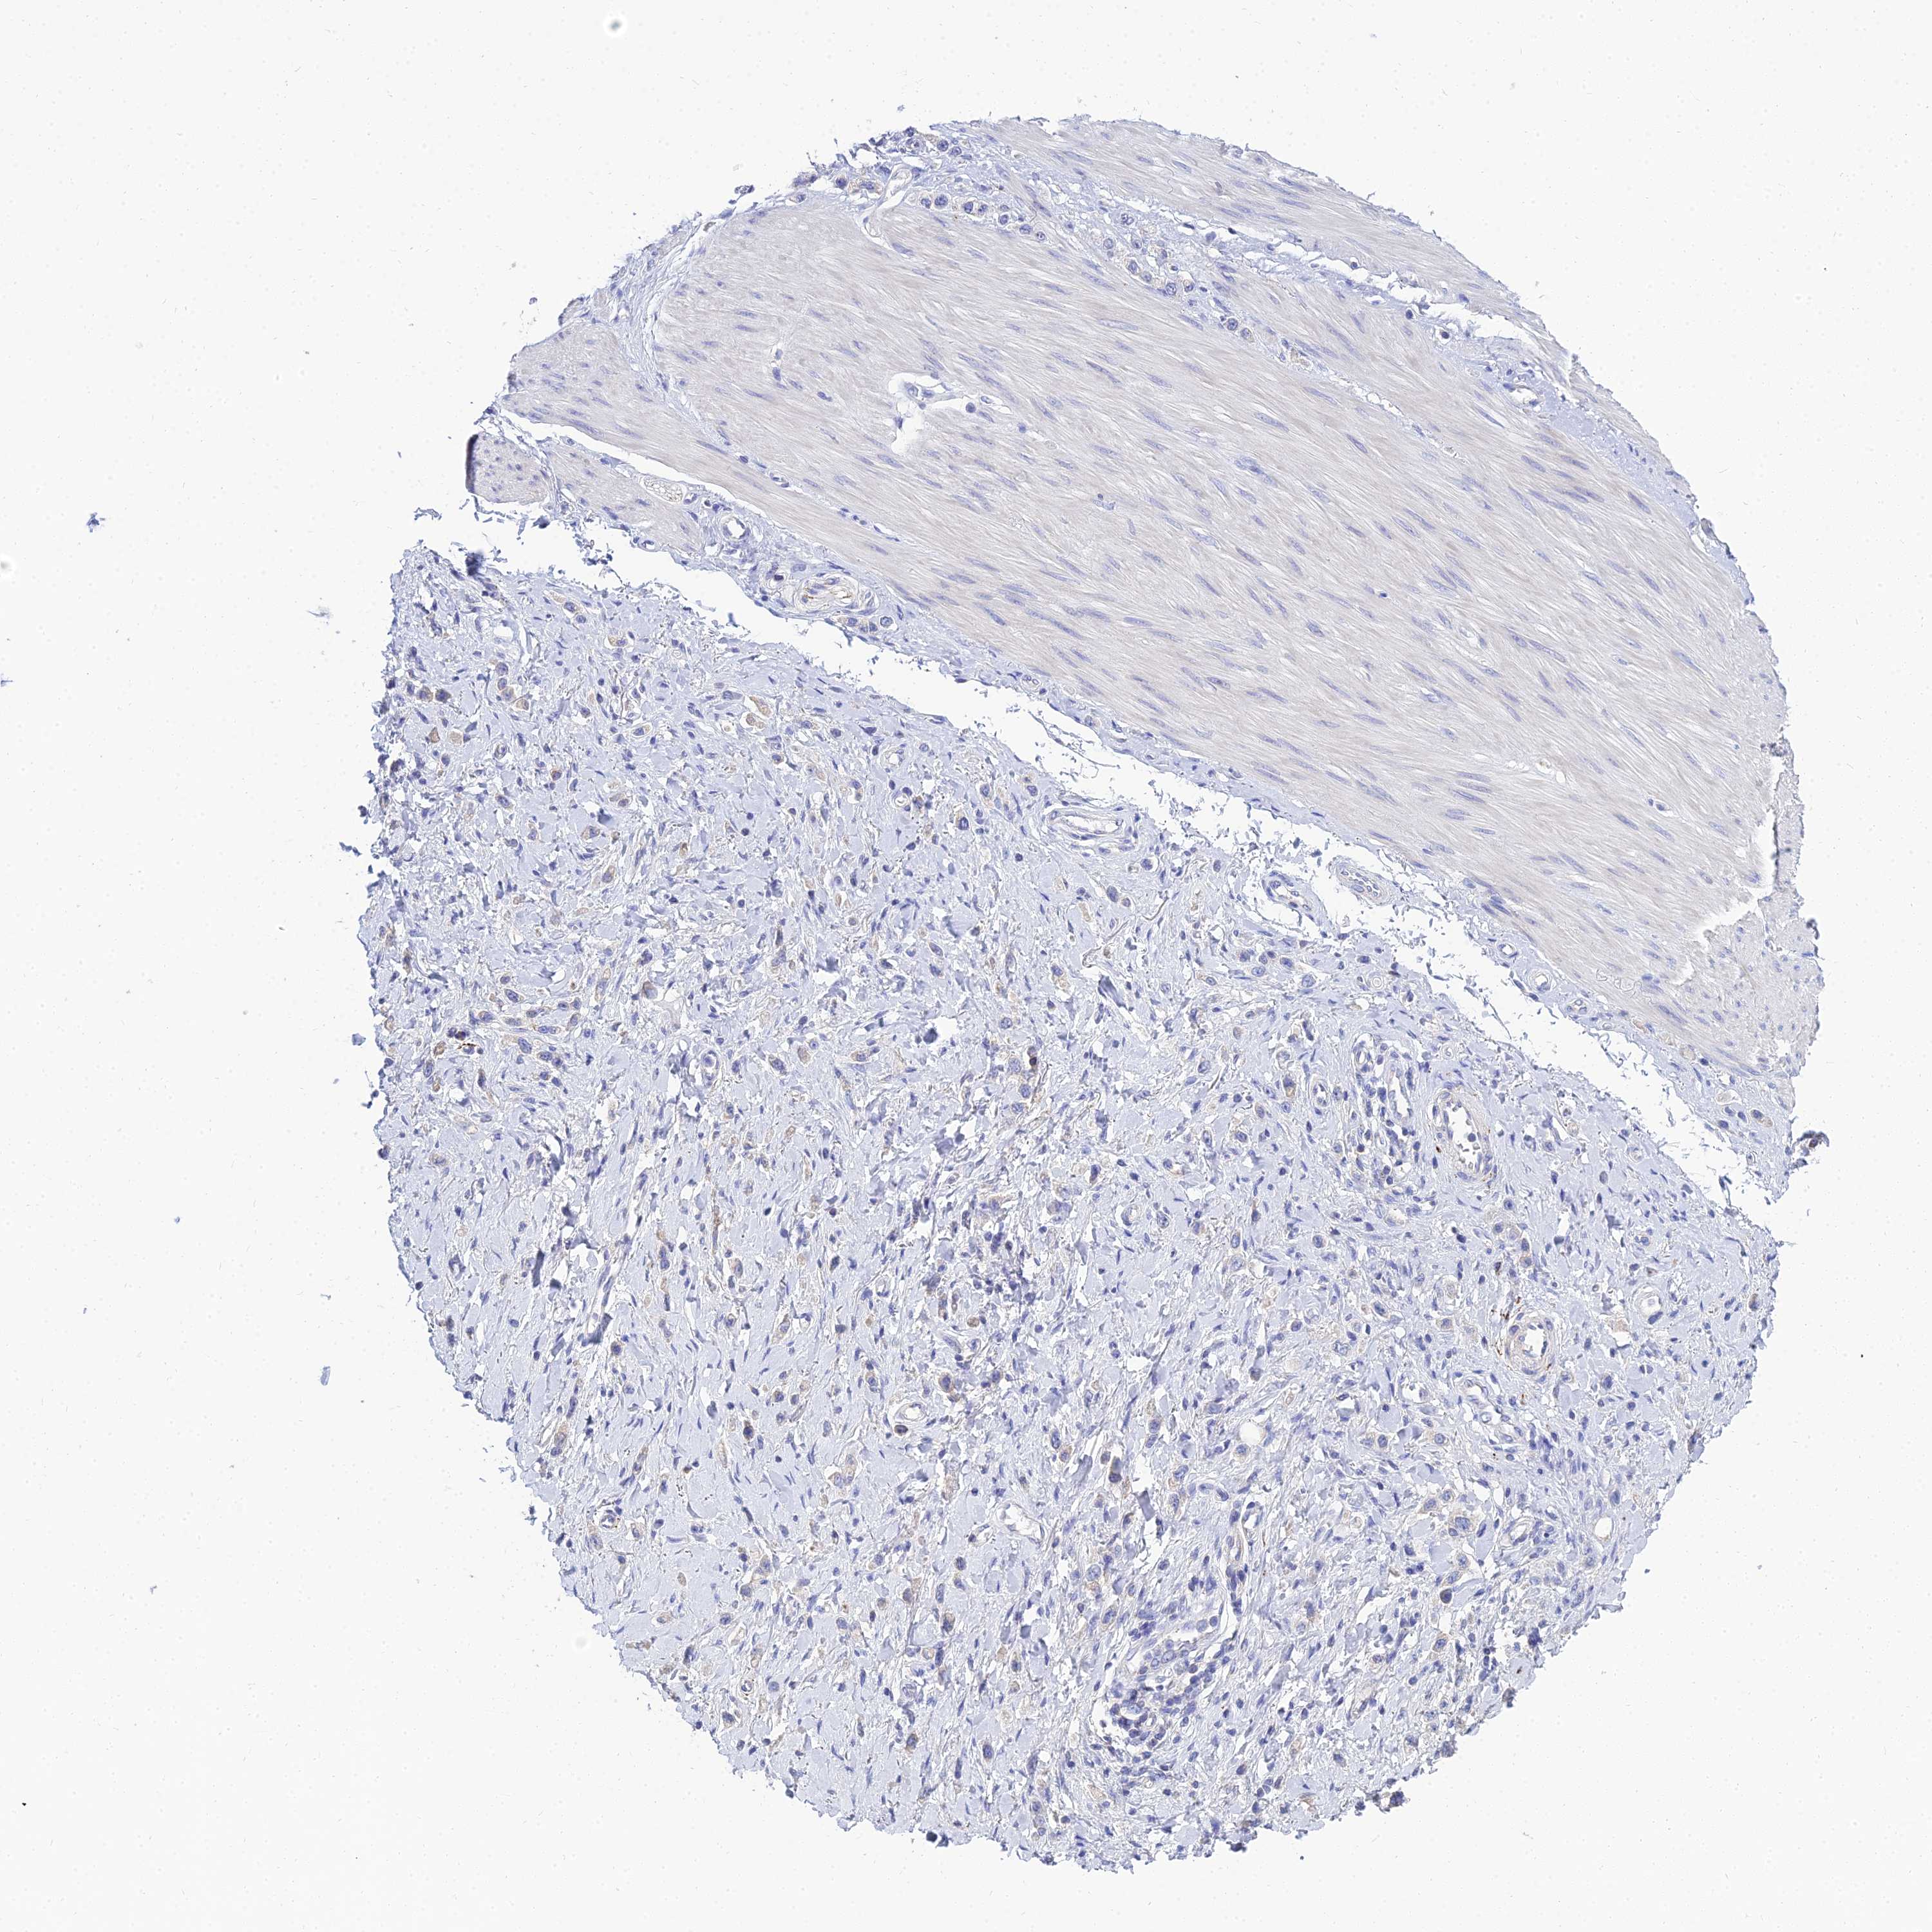

STOMACH CANCER - Protein expressioni

A mouse-over function shows sample information and annotation data. Click on an image to view it in a full screen mode. Samples can be filtered based on level of antibody staining by selecting one or several of the following categories: high, medium, low and not detected. The assay and annotation is described here.

Antibody stainingi

Antibody staining in the annotated cell types in the current human tissue is reported as not detected, low, medium, or high, based on conventional immunohistochemistry profiling in selected tissues. This score is based on the combination of the staining intensity and fraction of stained cells.

Each image is clickable and will lead to virtual microscopy that enables deeper exploration of all samples and also displays staining intensity scores, fraction scores and subcellular localization as well as patient and tissue information for each sample.

Antibody HPA044572

Antibody HPA056798

Antibody CAB016733

Antibody CAB034368

Staining

High

Medium

Low

Not detected

Intensity

Strong

Moderate

Weak

Negative

Quantity

>75%

75%-25%

<25%

None

Location

Nuclear

Cytoplasmic/membranous

Cytoplasmic/membranous,nuclear

Adenocarcinoma, NOS